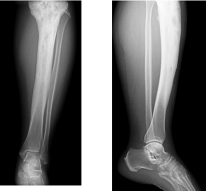

Osteofibröz displazi Campanacci hastalığı; nadir bir hastalıktır, tibia (kaval kemiği) ve fibulayı tutar. Özellikle tibianın 1/3 orta kısmında görülür. Tibia öne ve yana doğru eğilir. Kırık gelişmediği sürece ağrı olmaz. Patolojik kırk konservatif olarak tedavi edilir. Deformiteyidüzeltmek ya da deformite gelişmesini önlemek amacı ile cerrahi olarak tedavi edilir.